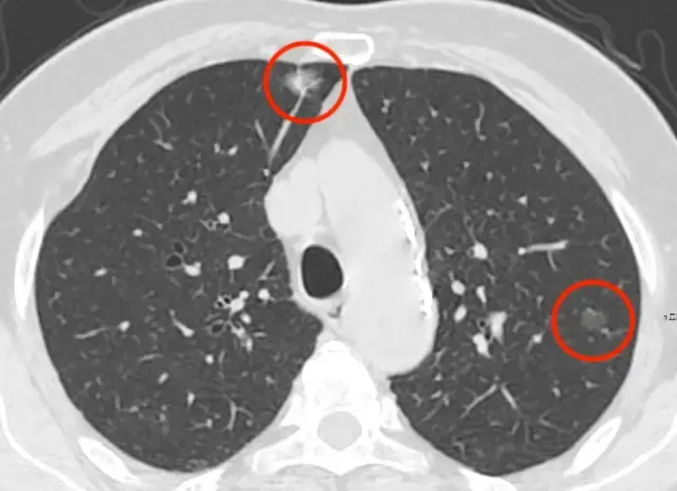

临床_上很多肺部疾病都以肺部多发性结节为主要的特征表现,所谓的肺部结节就是CT影像上肺部致密阴影病灶,多为圆形或者类圆形的,一般情况下阴影的直径会小于三厘米。早期肺部结节并不会引发不适症状且常常在体检中被发现,而肺部结节的诱因主要有五个。